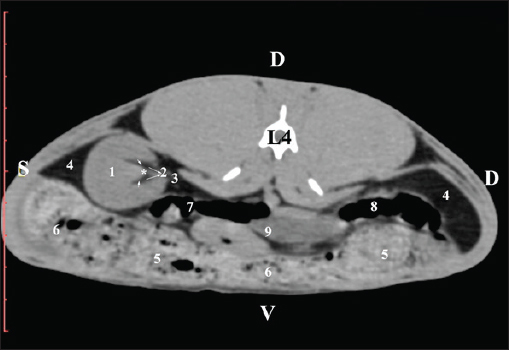

The pre-contrast anatomical scan at the L4 level provided data about the location of the renal pelvis within the renal sinus. The initial part of the pelvis renalis appeared as a distinct funnel-shaped hypoattenuated soft tissue, whose central part was widened and formed the recessus renalis. The transition of the narrowed end of the renal pelvis into the hypoattenuated left ureter was without a sharp boundary. The left kidney was in contact with the cecum, colon ascendens, and colon transversum ventrally. Crista renalis was observed as a hypoattenuated linear soft tissue finding (Figs. 10 and 11).

Fig. 10. Pre-contrast computed tomography (CT) anatomical scan of the regio-abdominis media at the cranial L4 edge level. (1) Ren sinister; (2) pelvis renalis and crista renalis; (3) ureter; (4) cecum; (5) colon ascendens; (6) colon transversum; (7) colon descendens; (8) adipose collections.

Fig. 11. Pre-contrast computed tomography (CT) anatomical scan of the regio-abdominis media at the caudal L4 edge level. (1) Ren sinister; (2) pelvis renalis; (3) ureter; (4) adipose collections; (5) cecum; (6) colon ascendens; (7) colon transversum; (8) colon descendens; (9) mesenterium; (white arrows) recessus renalis; (*) crista renalis.

The L5 scan revealed the caudal end of the left kidney. It was adjacent to some small intestinal segments, including the duodenal pars ascendens, ileum, cecum, and colon ascendens (Figs. 12 and 13).

Fig. 12. Pre-contrast computed tomography (CT) anatomical scan of the regio-abdominis media at the cranial L5 edge level. (1) Ren sinister; (2) adipose collections; (3) cecum; (4) colon ascendens; (5) jejunum; (6) pars ascendens of the duodenum; (7) colon transversum; (8) colon descendens.

Fig. 13. Pre-contrast computed tomography (CT) anatomical scan of the regio-abdominis media at the caudal L5 edge level. (1) Ren sinister; (2) adipose collections; (3) cecum; (4) colon ascendens; (5) colon transversum; (6) colon descendens.

The scan through L4 presented the funnel-shaped margins of the pelvis renalis as a relatively hypoattenuated soft tissue finding, whereas the kidney recesses were visualized in its central part. The crista renalis was hyperattenuated and nominated into the renal pelvis. The beginning of the ureter was medial to the left kidney (Fig. 18).

Fig. 18. Post-contrast computed tomography (CT) anatomical scan of the regio abdominis cranialis at the L4 level. (1) Ren sinister; (2) pelvis renalis; (3) ureter; (4) lien; (5) colon ascendens; (6) cecum; (7) colon transversum; (8) colon descendens; (9) mesenterium; (*) crista renalis; (black arrowhead) recessus renalis.

The extremitas caudalis was clearly visible at the L5 level. The capsula adiposa was relatively hypoattenuated and covered the capsula fibrosa. Меdially, the hyperattenuated ureter was visible (Fig. 19).

Fig. 19. Post-contrast computed tomography (CT) anatomical scan of the regio-abdominis cranialis at the L5 level: (1) Ren sinister; (2) adipose collections; (3) cecum; (4) colon ascendens; (5) colon transversum; (6) colon descendens; (7) mesenterium; (8) ureter; (9) aorta abdominalis; (10) v. cava caudalis; (*) cortex renalis; (**) capsula adiposa.